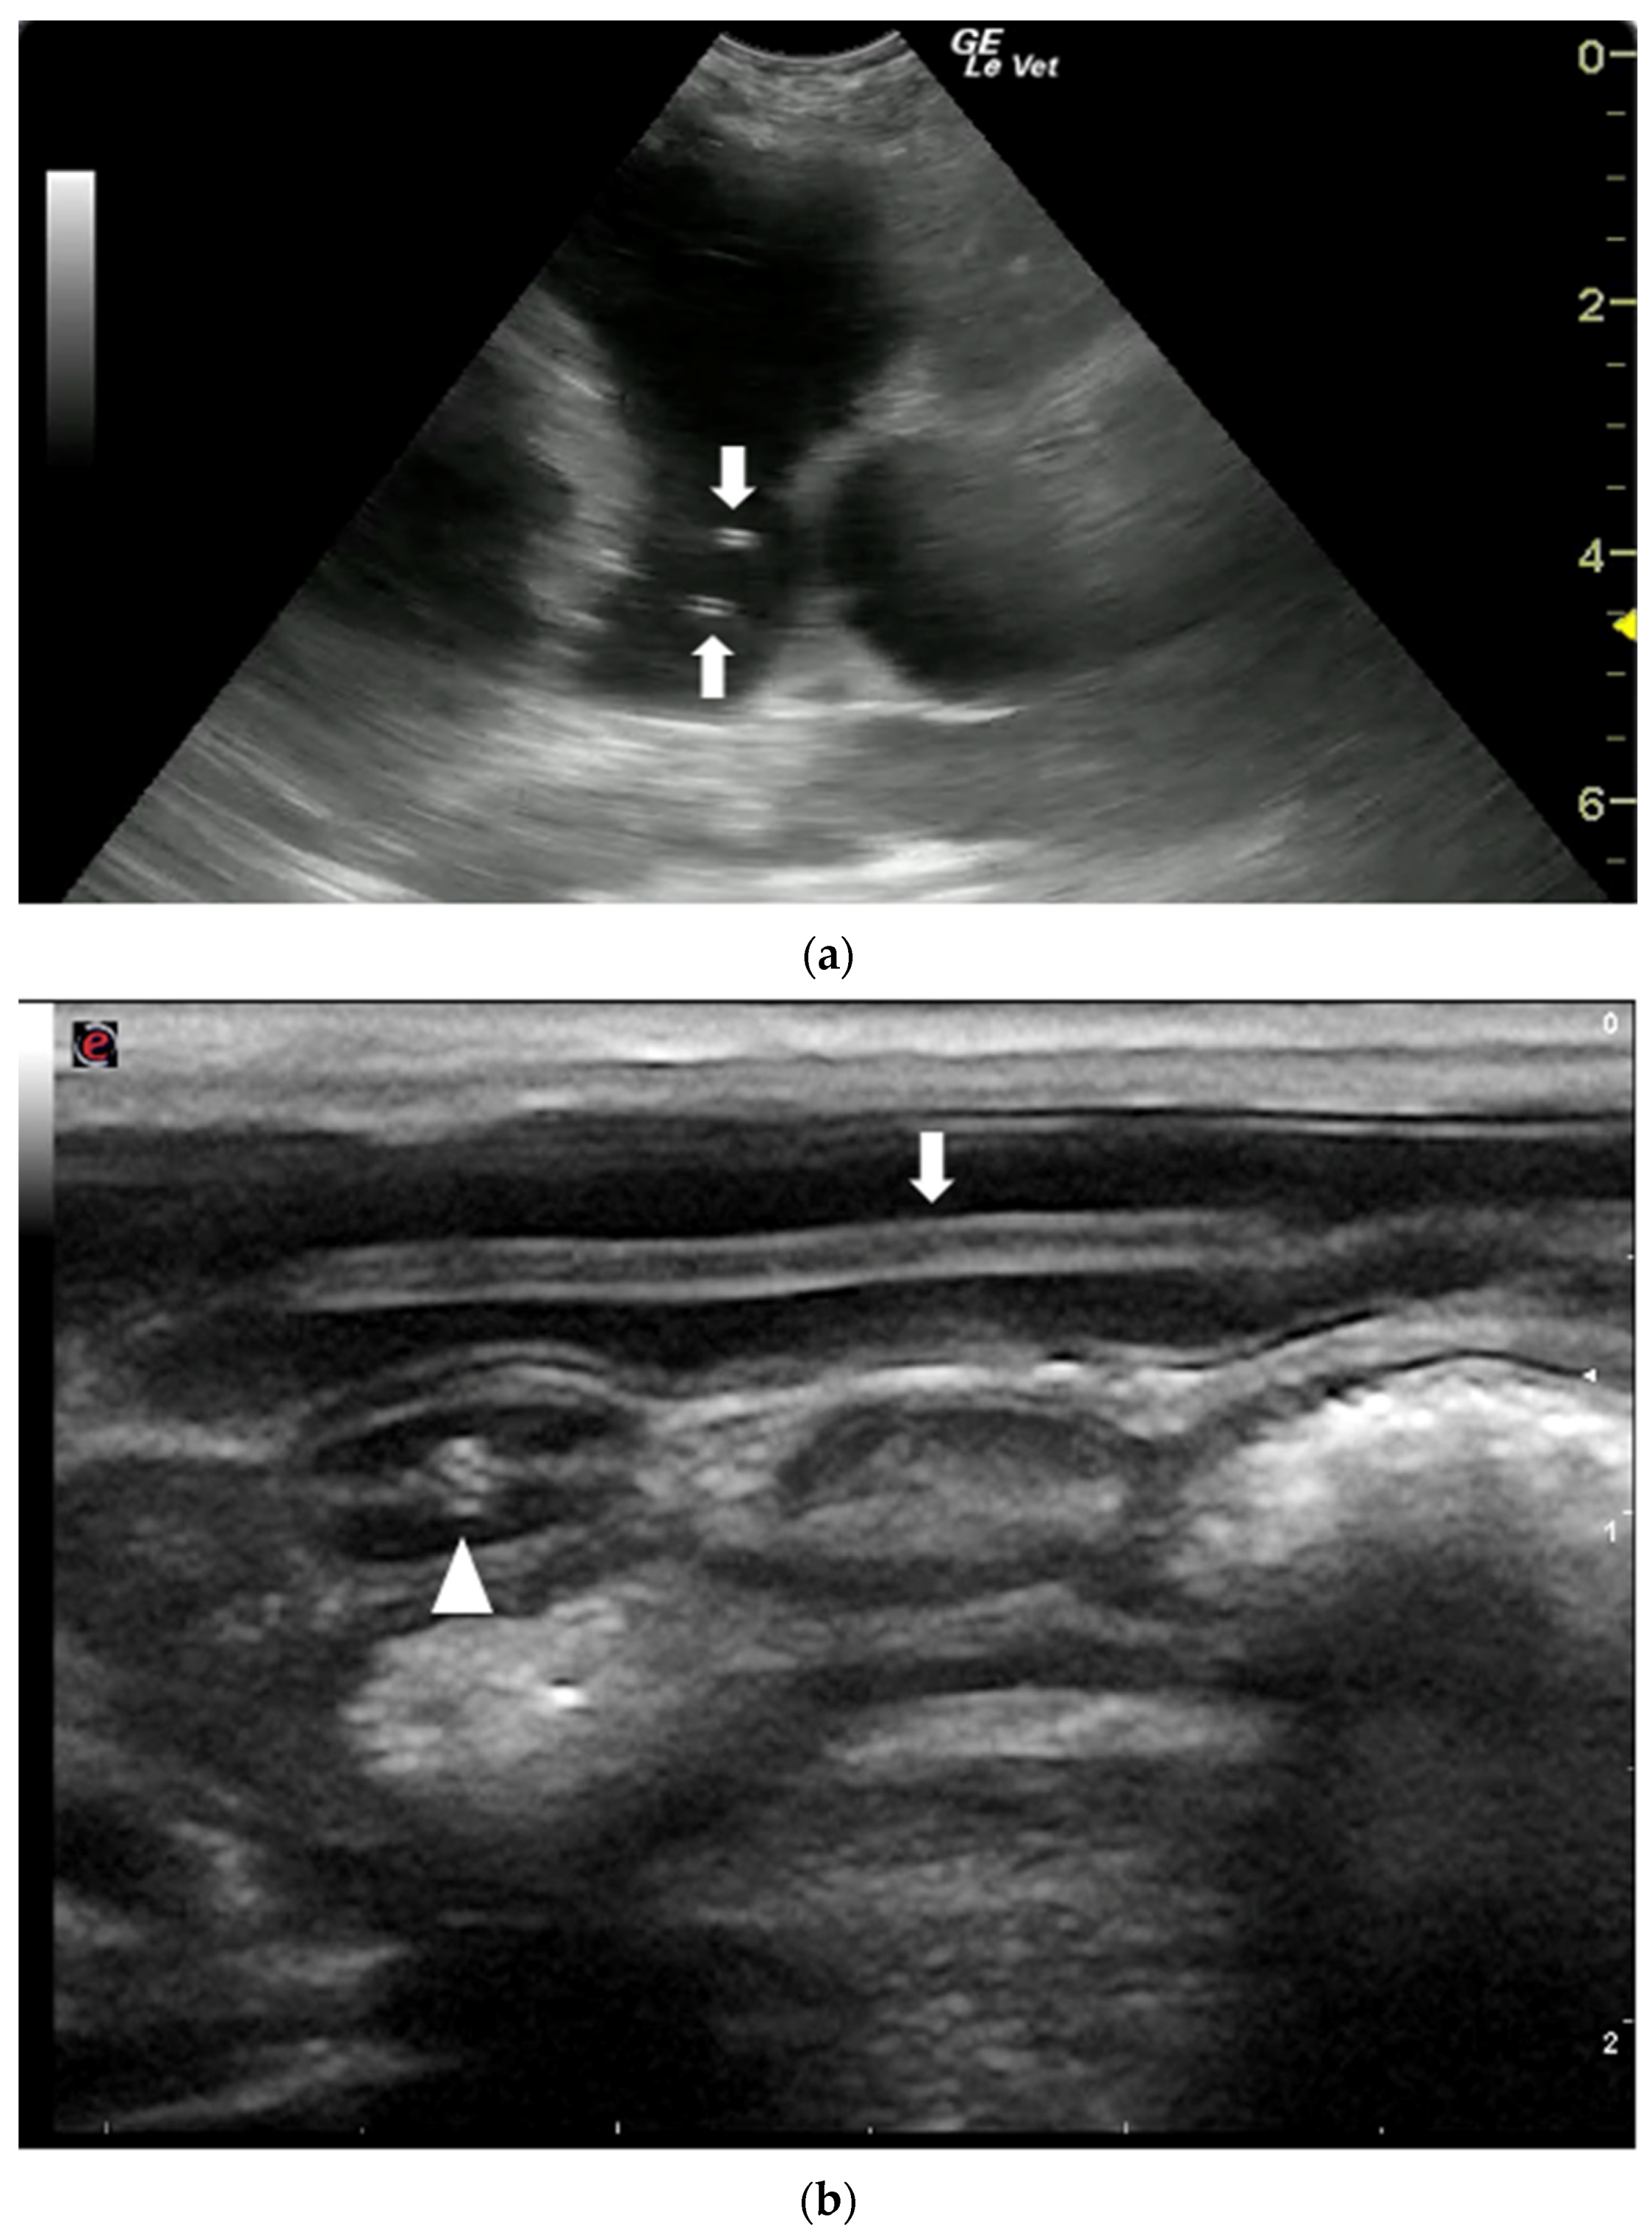

The US appearance of nematodes is due to the structure of the parasite which, in longitudinal section, appears as a linear “train track“ structure composed of two parallel hyperechoic lines, that represent the cuticle, separated by a narrow hypo/anechoic line constituted by the alimentary canal. In cross section, they have a “donut” appearance characterized by a hyperechoic circular wall with a hypo-anechoic center [58,59,60,61,62,63] (Figure 5).

Figure 5.

Ultrasonographic appearance of nematodes. (a) T. canis worms in the small intestine of a puppy, longitudinal (arrow) and transversal section (arrowhead) of the parasite. (b) Sections of adult D. immitis worms in the pulmonary artery of a dog (arrows). Courtesy of the Veterinary Teaching Hospital, University of Sassari (Italy).

Nematodes are easily recognized in US images. They are characterized by a linear structure composed of two parallel hyperechoic lines, separated by a narrow inner hypoechoic zone, in longitudinal sections, and a hyperechoic circular wall, with a hypo-anechoic center, in transverse sections (Figure 5). The nematode most commonly described by US in human medicine is Ascaris lumbricoides which can be visualized in the intestinal lumen and in the biliary tract of infected patients [60]. In veterinary medicine the species D. immitis and D. renale are the most easily identifiable due to their size and their localization in the cardiovascular lumen and in the kidneys, respectively. In canine and feline heartworm disease, US is a fundamental test to assess the severity of the disease and, consequently, to guide clinicians in therapeutic decisions. Moreover, US plays an important role in the diagnosis of heartworm disease in cats [67] and of aberrant D. immitis localizations in dogs and cats [75,76,77,78]. In both cases, negative Knott’s microfilarial and heartworm antigen tests may occur and, the direct US visualization of the adult parasites allows the disease to be diagnosed. However, in both dogs and cats, the lack of US evidence of parasites in the pulmonary arteries and/or in the right heart does not rule out infection [65,67,82]. Therefore, US images should always be interpreted considering the clinical findings and the results of other diagnostic tests.